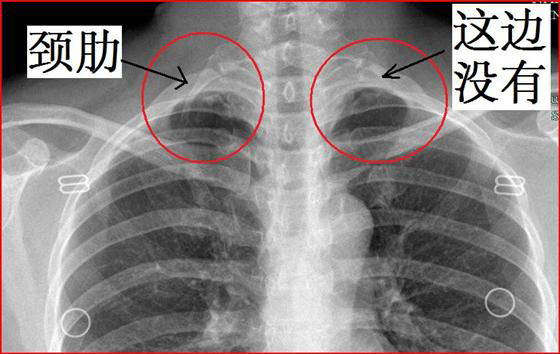

由于第7颈椎的横突异常增生,隆突形成肋骨,而使胸廓的出口狭小,以致出现神经和血管的压迫症状,此即颈肋综合征。劲肋综合征多见于中年人,因为人步入中年以后,颈肋软骨逐渐骨化,血管弹性差,胸廓出口的血管、神经容易受压。其临床表现主要有手臂疼痛,感觉异常,肤色苍白,手指发冷,患肢肌肉萎缩、软弱无力,其中以手掌尺侧小鱼际较明显。严重者可出现患肢瘫痪,感觉消失,甚至手指坏死现象。颈部触诊,可在患侧锁骨上凹中部触及质地较硬的肿块,在肿块下可以触及锁骨下动脉的搏动。如作颈椎X线摄片,可发现第7颈椎患侧横突异常,形成肋骨,即可明确诊断。

1、颈肋:第7 颈椎肋骨残存或横突过长,可改变出口的结构,易使臂丛跨越颈肋时受到压迫。有颈肋者不一定出现症状,只有出现症状者方需治疗。